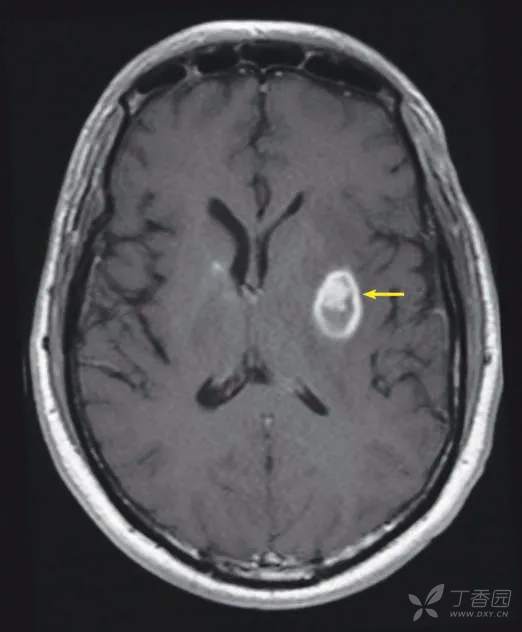

表现

轴位对比增强的T1WI显示左基底节区见一环形强化病变,并有大的偏心性结节(箭头)。

鉴别诊断

•弓形虫病

•其他感染

•恶性肿瘤

弓形虫病是指刚体弓形虫的感染,通过接触作为主要宿主的受感染猫的粪便,或者通过食用受感染的生肉,如猪肉而发生。从猫的粪便中摄取的卵囊和从被污染的肉中摄取的组织囊在血液中转变成速殖子。这些优先停留在中枢神经系统和肌肉组织,在那里它们发育成囊性缓殖子。在孕妇中,速殖子也可以穿过胎盘屏障并引起新生儿感染。弓形虫病的脑部病变通常是多灶性的,环形强化,大的不规则结节,表现为炎症,出血和坏死的综合。在大脑皮层和脑灰质深处,结节常常是偏心位(“不对称靶”征),在病理学上,对应于有穿透性血管的坏死脓肿。深部实质病变可显示为更加同心的表现(“同心靶”征),这是弓形虫病的特征性表现,病理上与中央出血相对应。相反,细菌性脓肿典型地是不伴有结节的光滑的环形强化。脑囊虫病表现为小的钙化性“点状”病变,病理上对应于寄生的头节。原发性囊性肿瘤和转移瘤通常是更加不均质的表现。